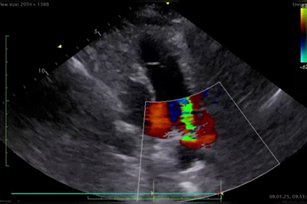

ÜRƏYİN YAD CİSİMLƏRİ Firuz İbrahimov, K.Q. Hüseynova, Ramil Əliyev, R.İ. Cəfərov Dərc edilib: AKJ N1 (27) 2025